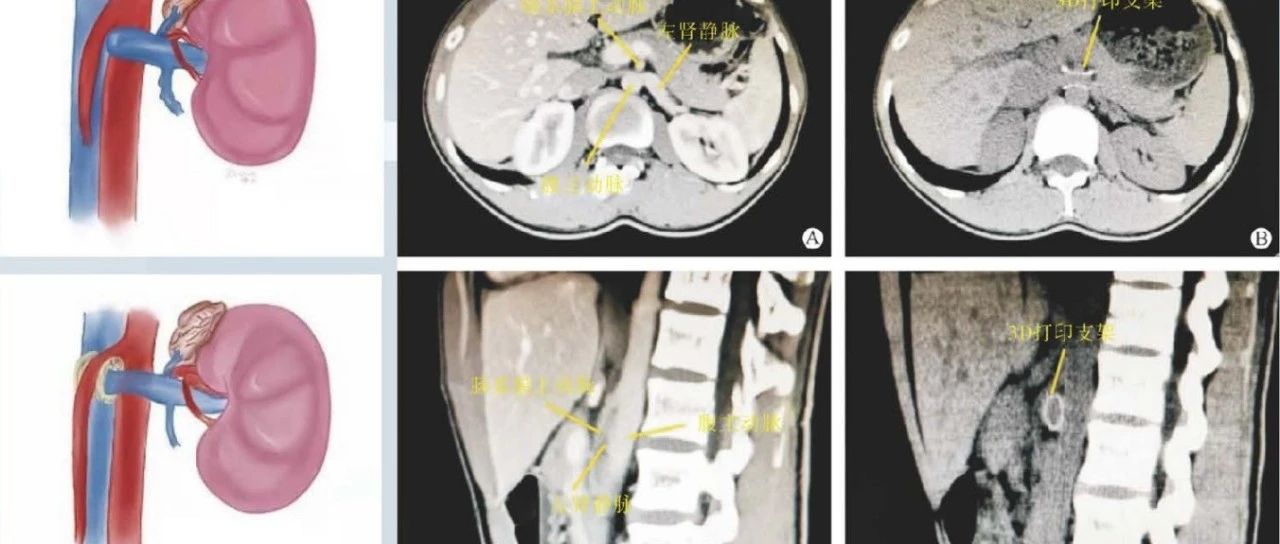

封面文章:3D打印支架治疗胡桃夹综合征合并IgA肾病的疗效观察

点击上方“蓝字”关注我们吧本文刊登在《现代泌尿外科杂志》2022年12期临床研究栏目,点击文末的“阅读原文”按钮,直达本刊官网,下载本文PDF。引用本文:何大立,张波,严奉奇,等.3D打印支架治疗胡桃夹综合征合并IgA肾病的疗效观察[J].现代泌尿外科杂志,2022,27(12):999-1003.3D打印支架治疗胡桃夹综合征合并IgA肾病的疗效观察何大立,张波,严奉奇,崔栋,焦勇(空军军医大学唐都医院泌尿外科...